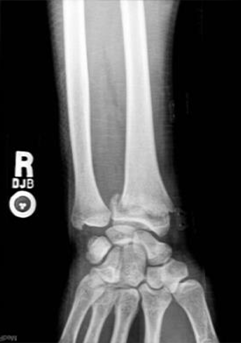

- Se solicita una radiografía AP de la muñeca derecha y se observa lo siguiente:

- Paciente orientada y cooperadora, facies dolorosa, se aprecia aumento de volumen y deformidad de la mano y muñeca derecha con forma de "dorso de tenedor".

Según las características de la paciente es posible integrar un diagnóstico clínico de osteoporosis y fractura de Colles en la muñeca derecha. De las siguientes opciones, ¿cuál no es un factor de riesgo para la osteoporosis?